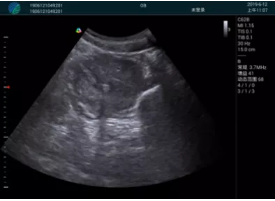

M20查看:囊內(nèi)回聲均勻,邊界清晰,囊壁光滑

M20引導(dǎo)抽吸術(shù)后囊腫消失,原區(qū)域空腔形成,脂肪層與腺體層架構(gòu)發(fā)生改變